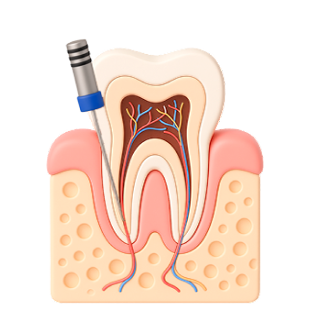

Установка имплантов вместо всех зубов предотвращает атрофию челюстной кости. Имплантат выполняет роль зубного корня и передает на челюстную кость жевательную нагрузку, аналогичную той, которую она испытывает при наличии собственных зубов. Не заметит разницы и сам пациент.